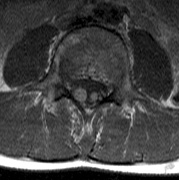

CNS hemangiomas are the most common tumor of VHL, affecting 60% to 80%, with a predilection for the cerebellum and spinal chord. An enlarging cystic component is a frequent finding in symptomatic tumors. Patients typically present in their early 30s; headaches or neck pain in affected individuals should not be ignored.172,173 On microscopy, CNS hemangiomas resemble retinal capillary hemangiomas. Their malignant potential is low.174 The treatment is surgical (Fig. 17, A and B).13

Fig. 17. Images from a 13-year-old boy with Von Hippel-Lindau syndrome. (a) Coronal postcontrast T1-weighted imaging reveals a cystic lesion with an enhancing nodule at the pial surface typical of a hemangioblastoma. (b) A second solid enhancing hemangioblastoma is seen at the craniocervial junction on a sagittal postcontrast T1-weighted image. (c) Associated cystic lesions (arrows) are seen within the pancreas.

Pancreatic lesions may be nonsecretory (most commonly cysts or cystadenomas) or secretory (islet cell tumor).179 In one study of 52 patients, 56% (29 patients) were found to have pancreatic lesions. The majority (19 of 29) had cystic changes only (Fig. 17C). Pancreatic lesions were the only abdominal manifestation of disease in 6 of 52 patients.180 In a separate study, pancreatic cysts did not show significant progression on follow-up examinations over an average period of 5 years.181 Like pancreatic cysts, islet cell tumors appear to be frequently asymptomatic.182